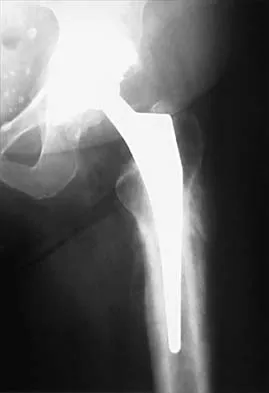

Figure 24 shows the radiograph of an otherwise healthy 56-year-old patient who reports hip pain after undergoing a primary cementless hip replacement 4 months ago. The next most appropriate step should consist of

Explanation

Periosteal new bone formation is a warning sign of prosthetic infection. Indomethacin may prevent heterotopic ossification if given early enough; however, it is irrelevant in this patient. A C-reactive protein and a sed rate are useful screening studies that add to the predictive value of the radiographs and may be performed routinely if sepsis is suspected. A bone scan obtained 4 months after surgery would show increased uptake in all cases. If results of a sed rate and C-reactive protein are normal, then a biopsy should be considered to rule out a neoplasm.